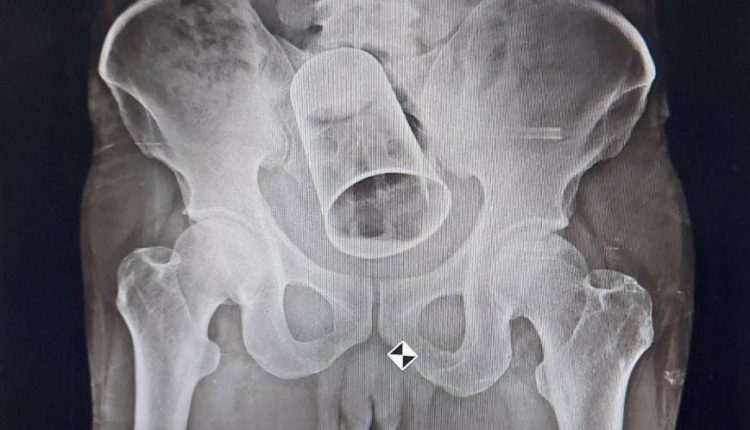

ପେଟ ଭିତରୁ ବାହାରିଲା ଷ୍ଟିଲ ଗ୍ଲାସ୍; ସୁରତରେ ପଶିଥିଲା, ବ୍ରହ୍ମପୁର ଏମ୍‌କେସିଜିରେ ବାହାରିଲା

ବ୍ରହ୍ମପୁର: ବ୍ରହ୍ମପୁର ସ୍ଥିତ ମହାରାଜା କୃଷ୍ଣଚନ୍ଦ୍ର ଗଜପତି ଭେଷଜ ମହାବିଦ୍ୟାଳୟ ଏବଂ ଚିକିତ୍ସାଳୟରେ ରବିବାର ଏକ ଭିନ୍ନ ଧରଣର ଅ​‌ସ୍ତ୍ରୋପଚାର କରାଯାଇଛି । ଜଣେ ବ୍ୟକ୍ତିଙ୍କ ପେଟ ଭିତରେ ଥିବା ଏକ ବଡ ଷ୍ଟିଲ ଗ୍ଲାସକୁ ଅ​‌ସ୍ତ୍ରୋପଚାର କରି ବାହାର କରାଯାଇଛି।

ଏହା ପରେ ତାଙ୍କର ଅ​‌ସ୍ତ୍ରାେପଚାର କରି ଗ୍ଲାସ ବାହାର କରିବାକୁ ଡାକ୍ତରମାନେ ନିଷ୍ପତ୍ତି ନେଇଥିଲେ। ଶଲ୍ୟ ଚିକିତ୍ସା ବିଭାଗ ମୁଖ୍ୟ ପ୍ରଫେସର ଡା. ଚରଣ ପଣ୍ଡାଙ୍କ ନିର୍ଦ୍ଦେଶ କ୍ରମେ ସହକାରୀ ପ୍ରଫେସର ଡା. ସଞ୍ଜିତ କୁମାର ନାୟକ, ଡା. ସୁବ୍ରତ ବରାଳ, ଡା. ସତ୍ୟ ସ୍ବରୂପ, ଡା. ପ୍ରତିଭା ଓ ତାଙ୍କ ଟିମ ଦୀର୍ଘ ଦୁଇ ଘଣ୍ଟା ଧରି ସଂପୃକ୍ତ ବ୍ୟକ୍ତିଙ୍କ ଅ​‌​‌ସ୍ତ୍ରାେପଚାର କରିଥିଲେ।

ସଫଳ ଅ​​‌ସ୍ତ୍ରାେପଚାର ସହ ବ୍ୟକ୍ତିଙ୍କ ଅନ୍ତଃ ନଳୀ କଟାଯାଇ ସେହି ଗ୍ଲାସକୁ ବାହାର କରାଯାଇଥିଲା। ବର୍ତ୍ତମାନ ସେହି ବ୍ୟକ୍ତିଙ୍କ ଚିକିତ୍ସା ଜାରି ରହିଥିବା ବେଳେ ସେ ସୁସ୍ଥ ହେଉଥିବା ଡାକ୍ତରମାନେ କହିଛନ୍ତି।